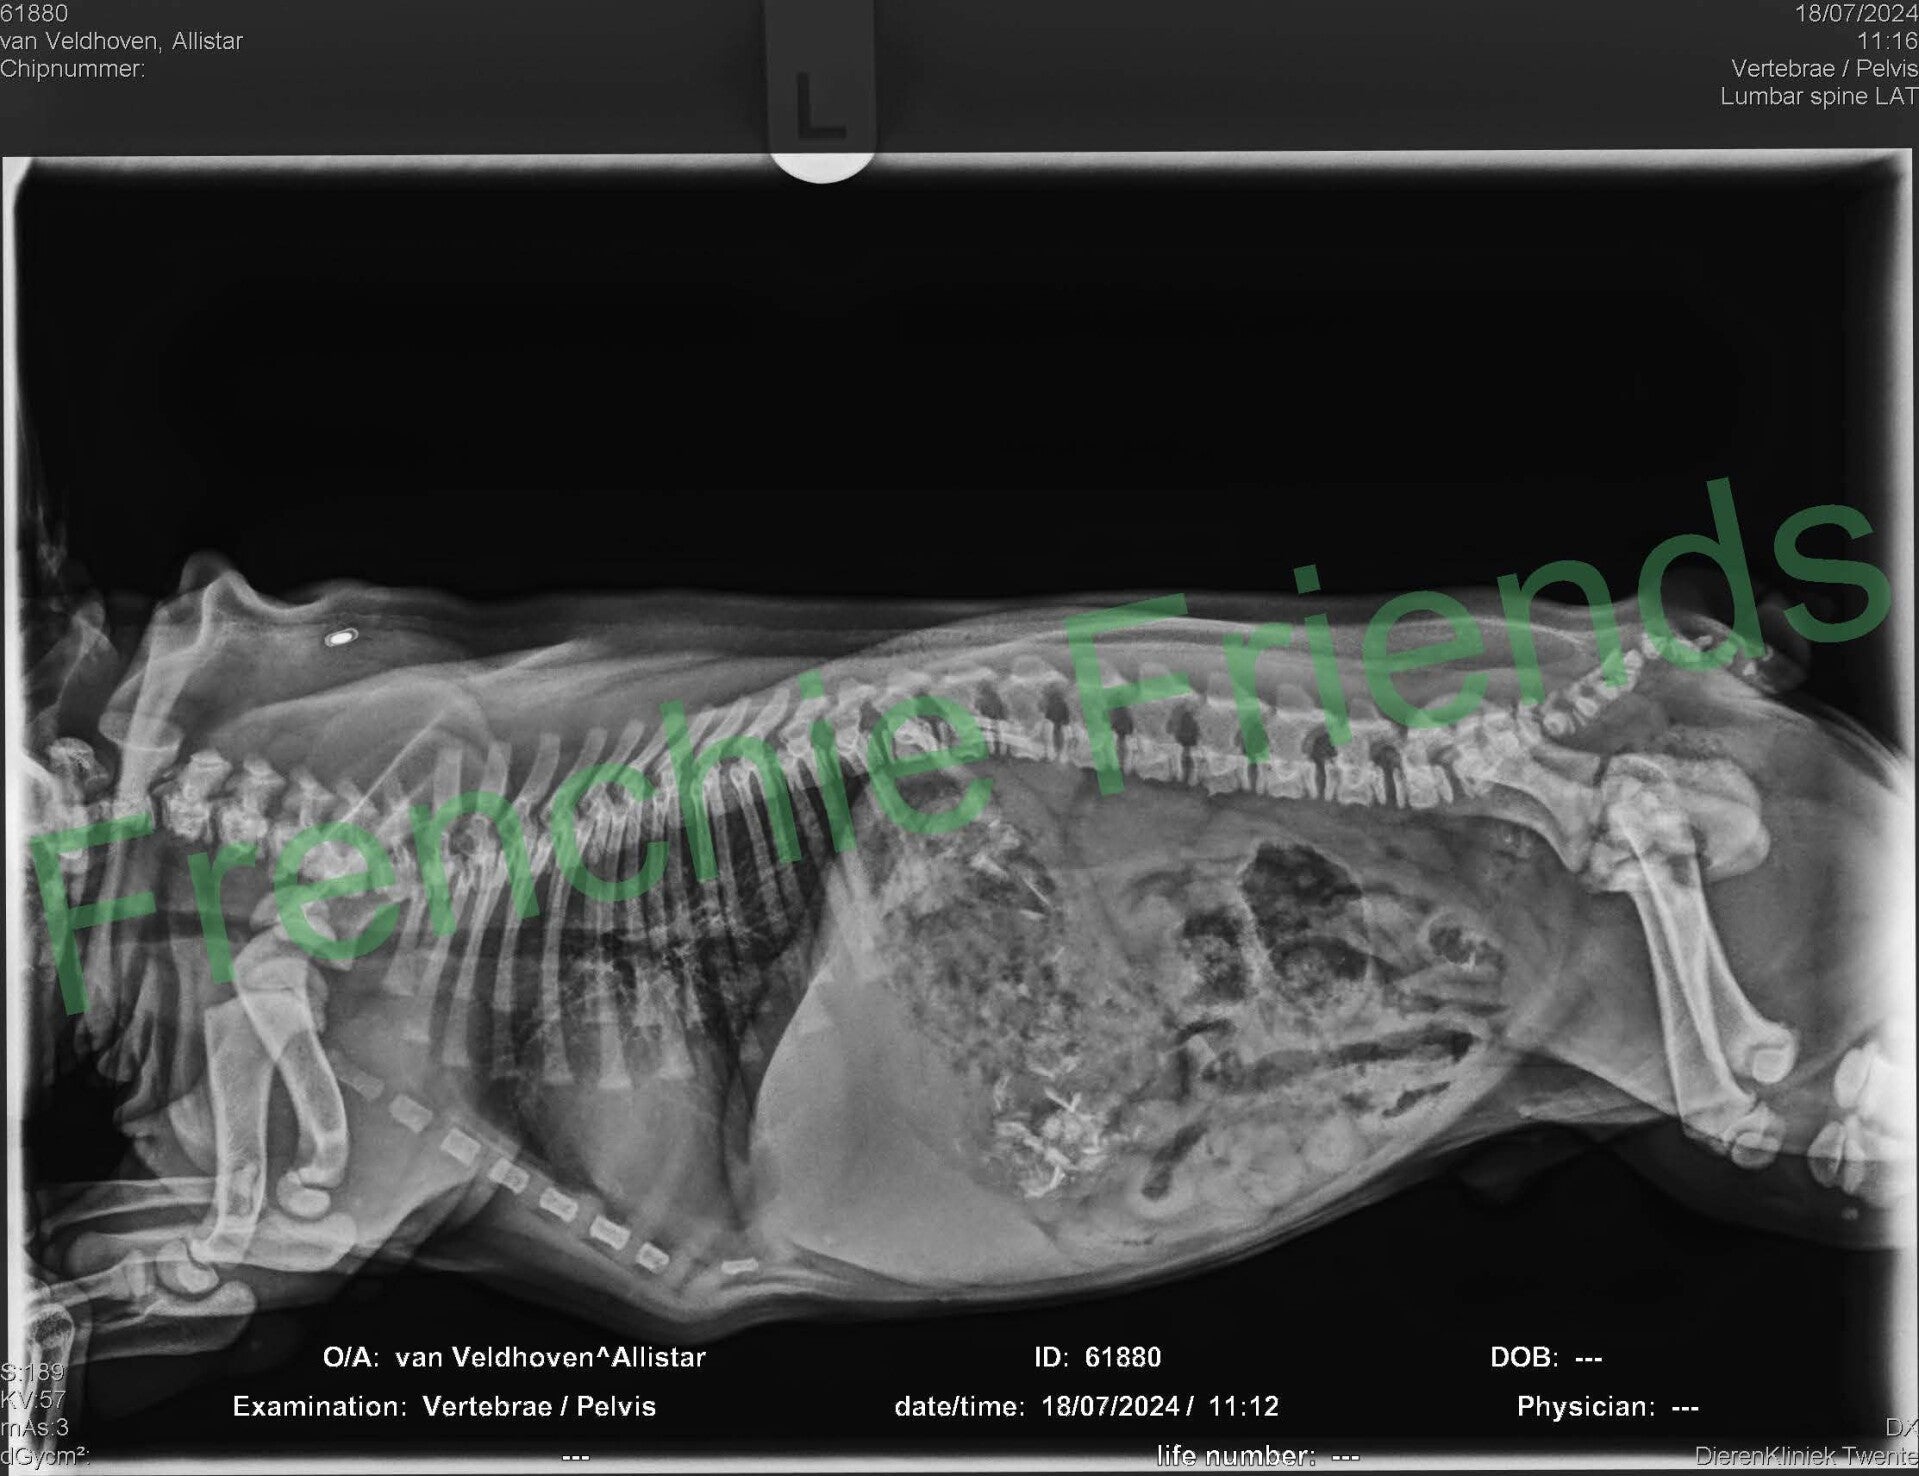

Op de röntgenfoto hadden we al gezien dat er 7 pupjes verwacht werden en alsof ze het al jaren zo deed perste Indy zonder problemen het ene na het andere pupje naar buiten. Bij nummer 5 werd het even spannend, maar mede dankzij mijn hulplijn met Esther, is ook dit pupje uiteindelijk goed en gezond ter wereld gekomen.

Om 16:30 uur kwam de tweede, ook een brindle reutje. Met 210 gram beduidend kleiner dan zijn grote broer; Allistar (Nu Elvis). Elvis woont bij mijn vrienden Linda en Dennis hier in de buurt. Hem zien we nog regelmatig!